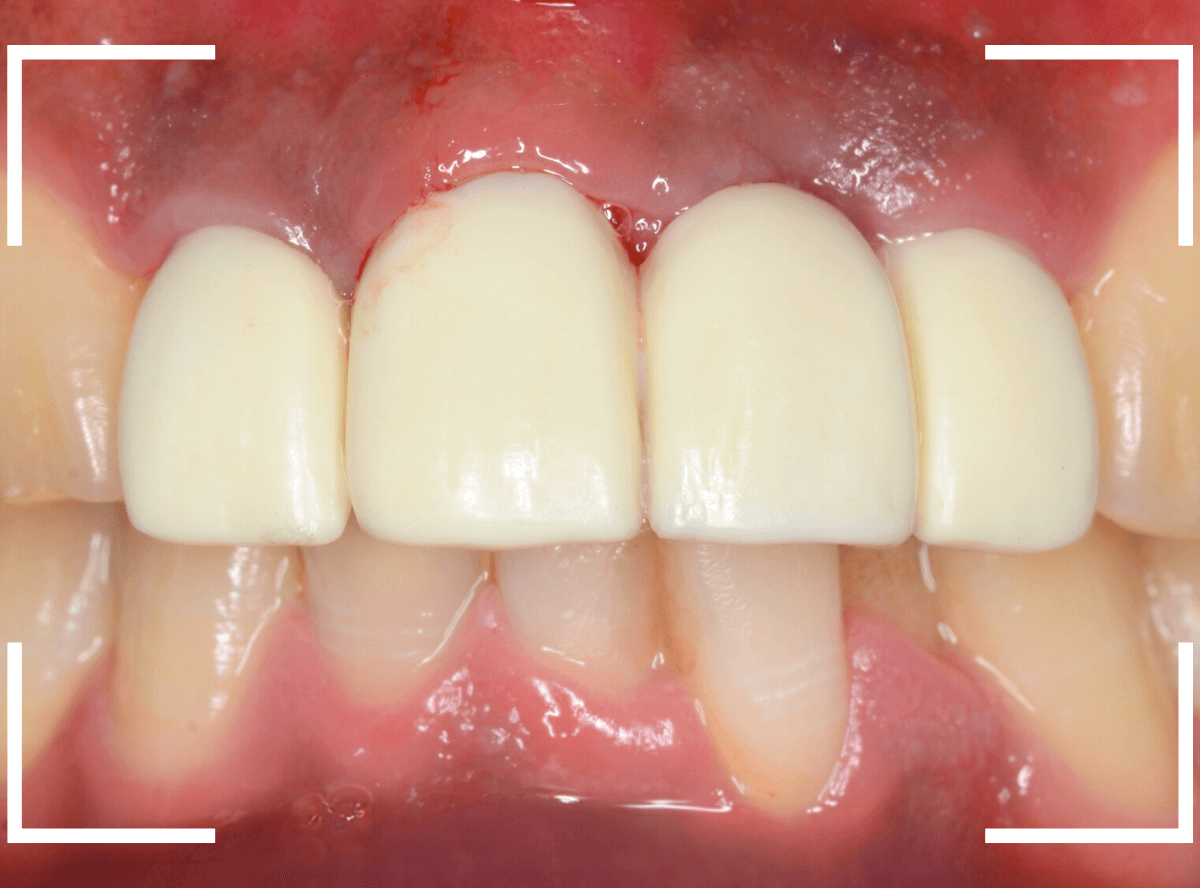

今回は、上の前歯のセラミックの形が気になるので、大分時間も経っているので新規に作り直したいというご希望の患者さんのお話です。

たしかに、隣の歯に比べてかなり下に下がってしまっています。

裏側を見ると少し歯肉が腫れています。

歯周病の治療と並行して、セラミックの作り直しをすることになりました。

さし歯の中には大きなメタル・コアが入っています。。。

さし歯の周りの歯肉が若干黒ずんでるのも、これが原因でしょう。

せっかくさし歯をやり直すのであれば、このメタル・コアもやりなおしたいところです。

かなり怖かったですが、患者さんにも頑張っていただいて、さし歯を除去後、時間をかけて慎重にメタルコアを除去しました。

無事にメタルコアを除去できましたので、ファイバーコアに置き換えます。

歯肉の治療がひと段落したところで、ジルコニア・セラミックで再製しました。

治療前と治療後の比較、前から見たところです。

患者さんにも満足いただけまして、ホッとしました。

裏側の歯肉も綺麗に治りました。

セラミックの表面はつるつるしていますので、歯周病の原因になるプラークがたまりづらく、治療後の経過も期待できます。